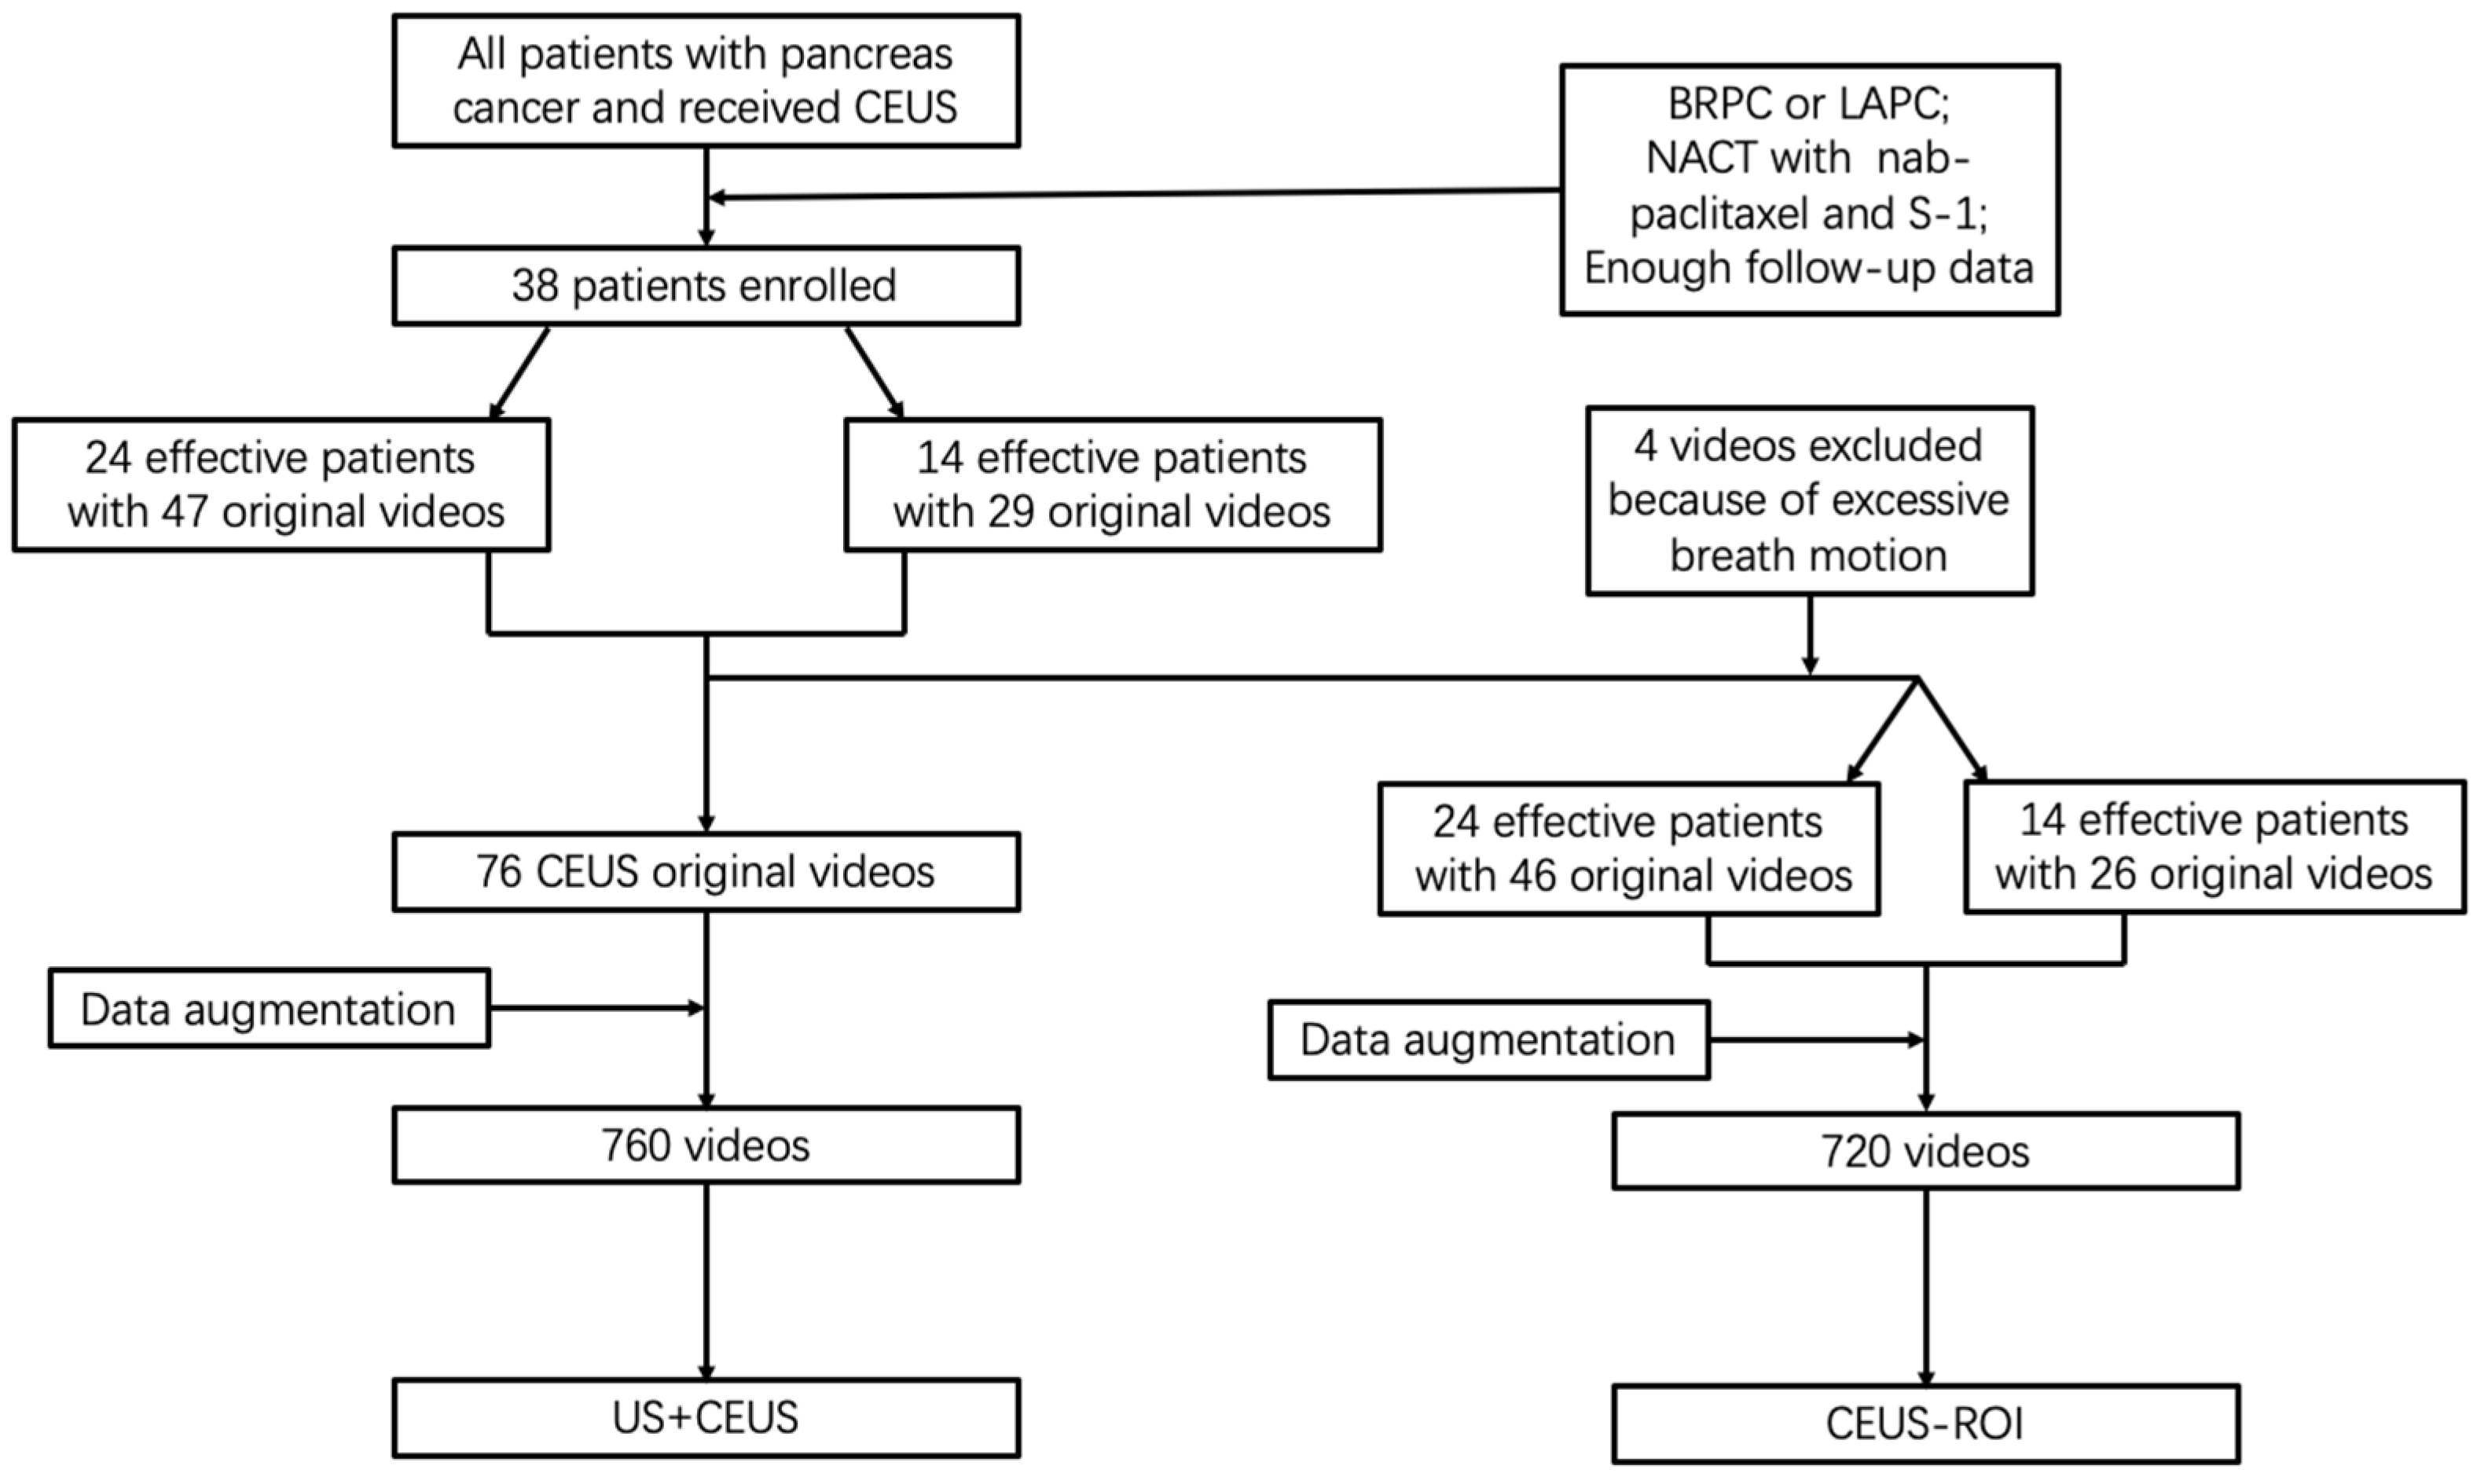

2.1. Patient Enrollment

2.3. CEUS Video Preprocessing